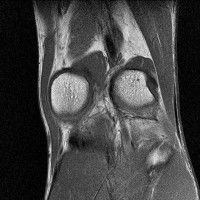

무릎 mri 간단히 봐주실 수 있으시나요 ㅠㅠ

안녕하세요 8년전 십자인대 수술하고 최근 무리한 운동에 무릎 불편감이 생겨서

mri 찍었습니다.

진단결과는 첫 찍은 병원에서 활액막염 이라는 진단을 받았습니다. 혹시 봐주실 수 있으실까요?

올라온 MRI가 단편적이라서 정확한 진단에 어려움이 있지만 십자인대에는 큰 이상이 있지는 않은것 같으며, 무릎관절내 물이 있는 것으로 보아 활액막염의 진단이 맞을 것 같습니다.

하지만 단편적인 영상이기 때문에 촬영병원에서 정확한 판독지 등을 받으시는 것이 좋겠습니다.